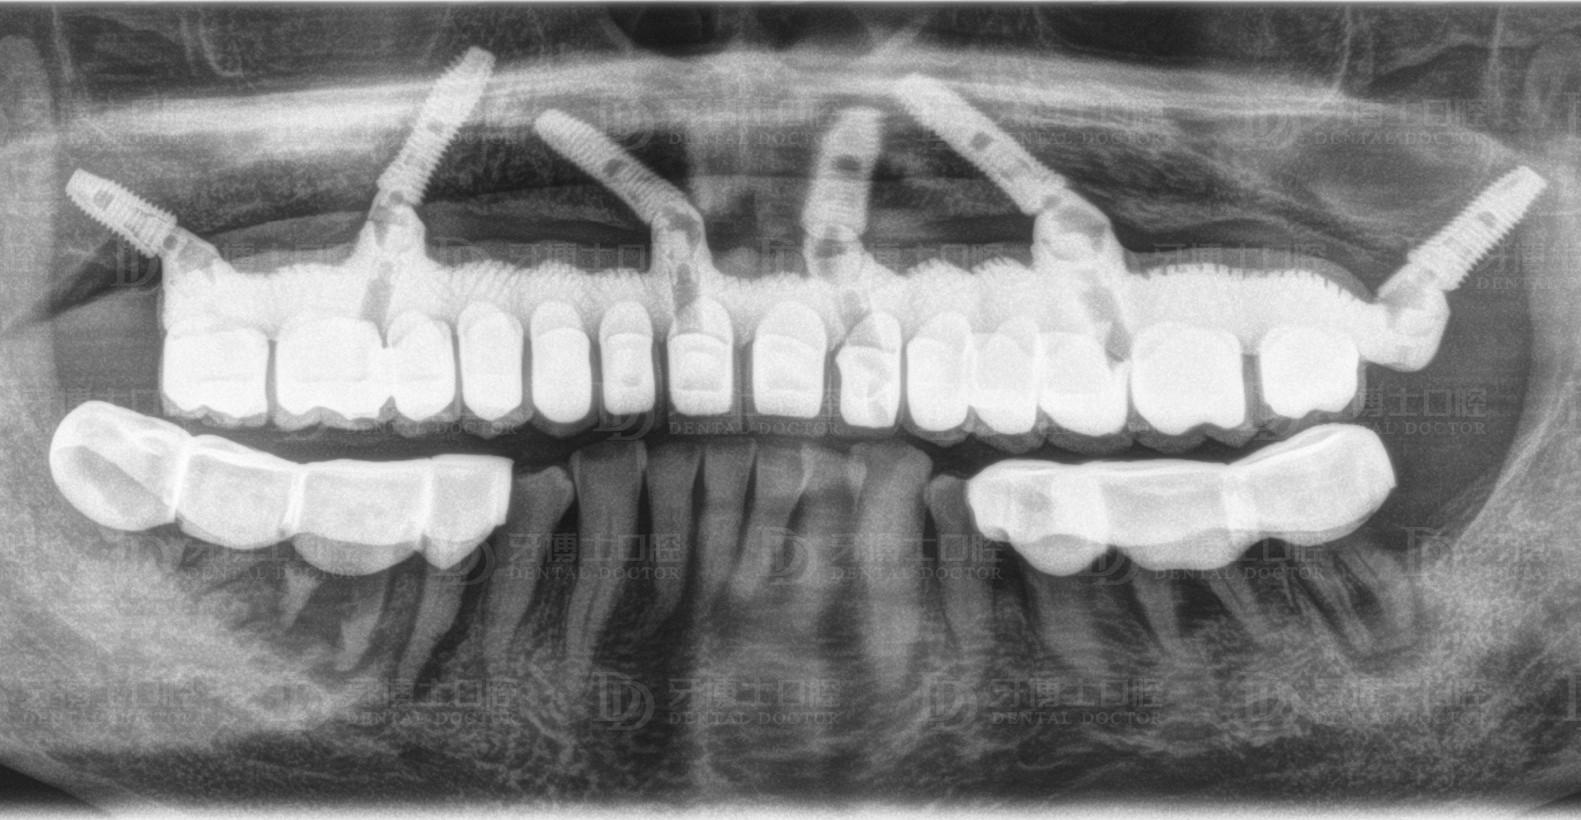

醫(yī)生根據(jù)他的骨量,設計了負重種植6顆恢復半口牙的方案,上午種牙,下午戴牙。種牙1個月后,精神狀態(tài)好,種牙3個月后,整個人圓了一圈,周老激動地跟醫(yī)生說了好些感謝的話,感慨老年生活從未這么順心過。

上半口種植6顆

All-on-4/6種植是一項高深精密的手術,對醫(yī)生技術、醫(yī)療設備的要求嚴格。因為種植牙上午種,下午就得受力,所以醫(yī)生需要辨別骨頭的質(zhì)量、密度,種進去的每一顆植體擁有35牛的扭力,如果植體很松,戴上牙冠后便會搖晃,就意味著種植失敗,這是種植技術的難點之一。

另外,務必基臺與植體高度結(jié)合。很多地方?jīng)]辦法開展種植牙技術的主要原因就在于此。